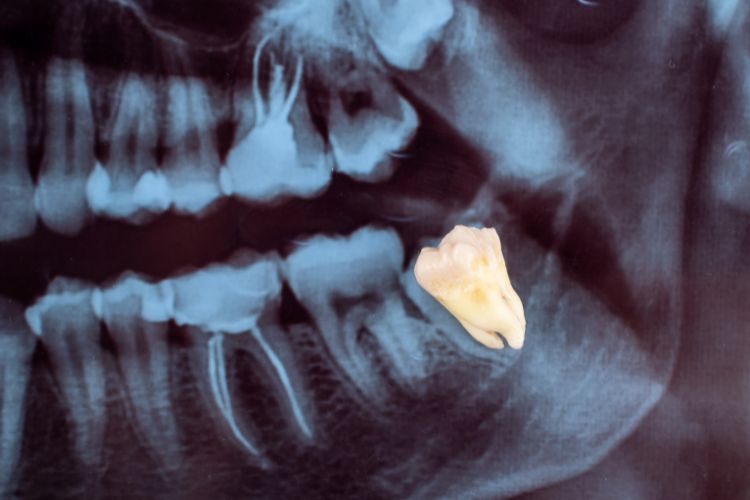

- Impactación de las muelas del juicio. Cuando las muelas del juicio no tienen suficiente espacio para emerger correctamente, pueden causar dolor y molestias.